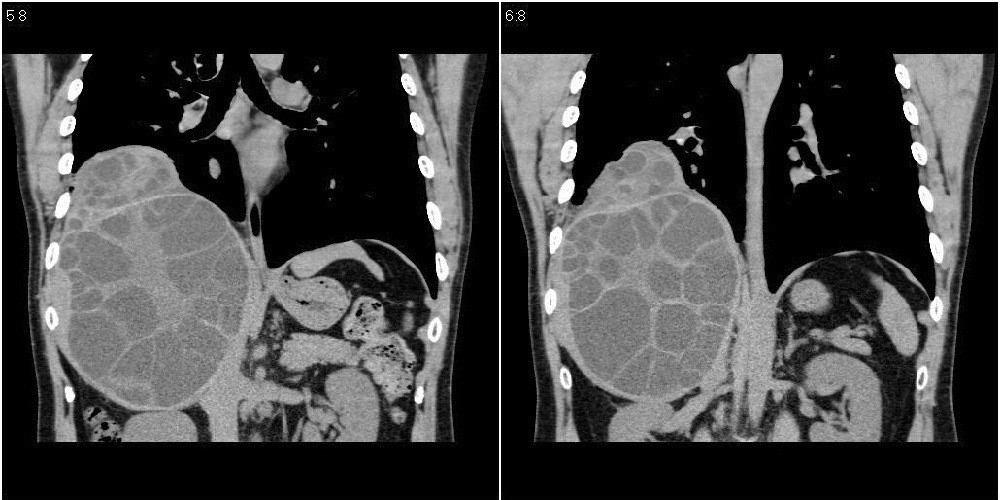

该患者70岁男性,手术后10年,现复查。2008年6月份本人曾经发过一极其类似的病例,只是部位略有差异。

多囊肝

肝脏多房性包虫囊肿

水上浮莲征,肝包虫囊肿。

肝脏及右侧胸腔包虫病。

大囊套小囊!肝脏多房性包虫囊肿